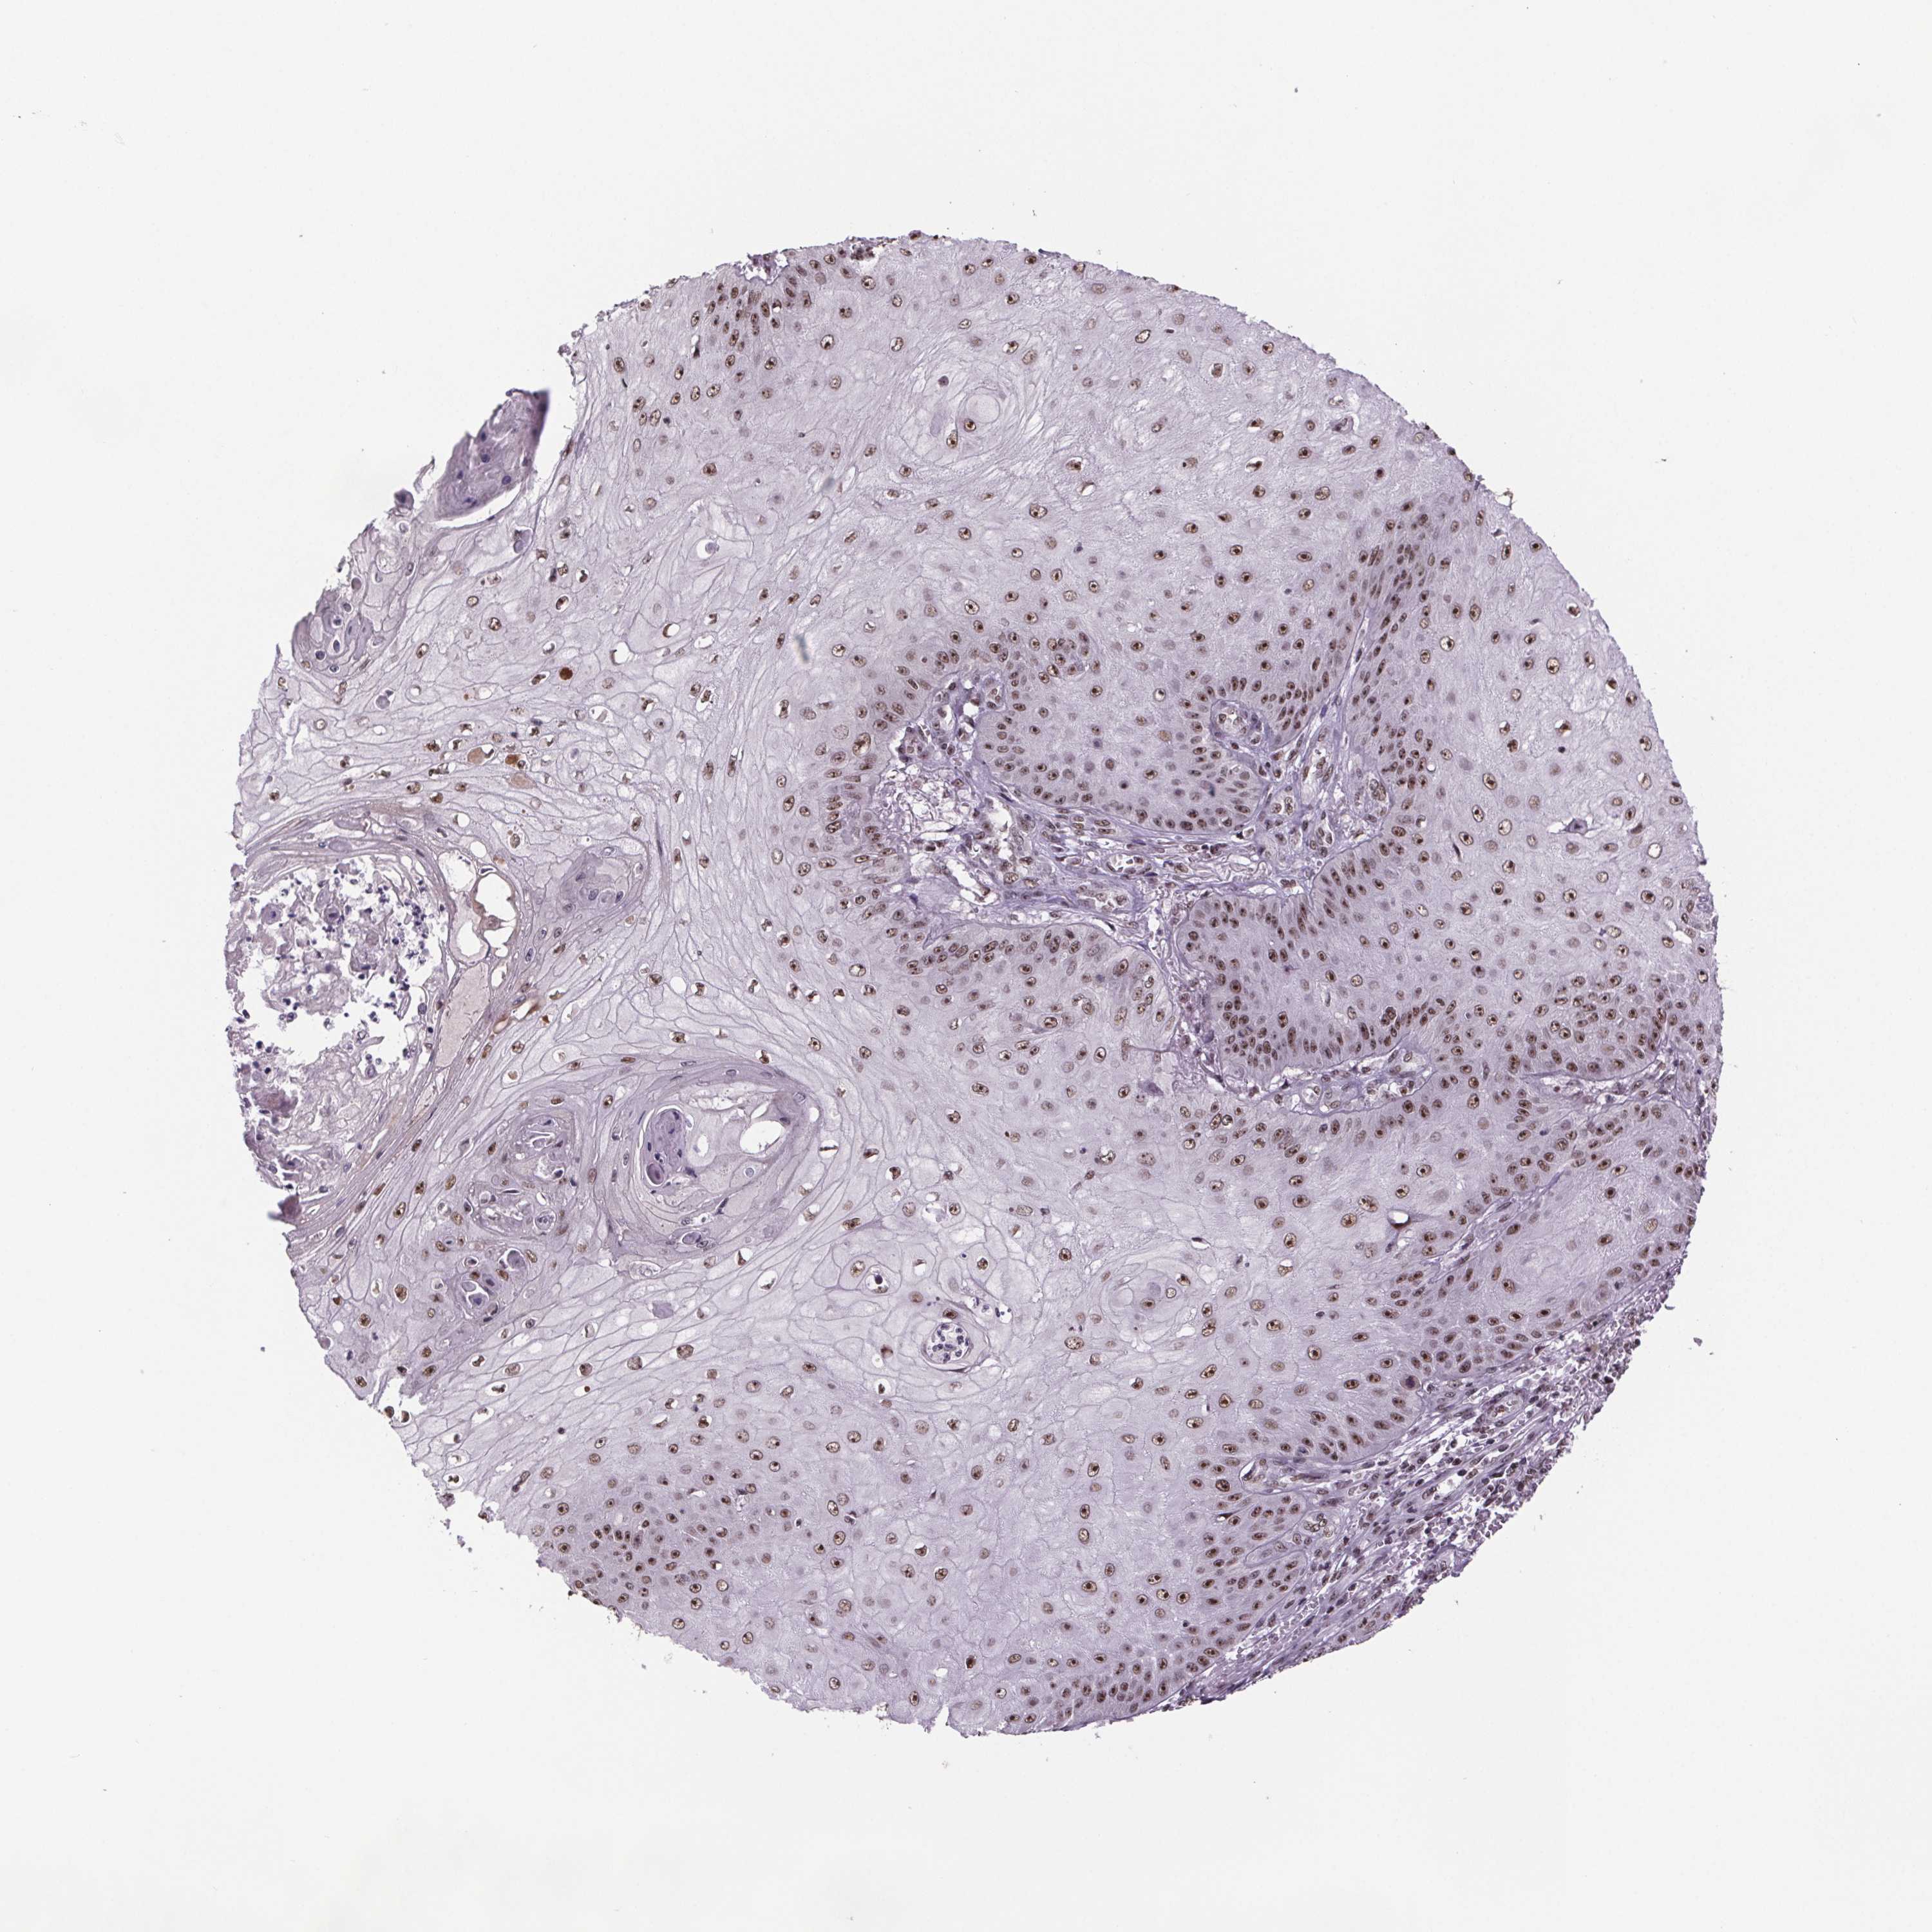

SKIN CANCER - Protein expressioni

A mouse-over function shows sample information and annotation data. Click on an image to view it in a full screen mode. Samples can be filtered based on level of antibody staining by selecting one or several of the following categories: high, medium, low and not detected. The assay and annotation is described here.

Antibody stainingi

Antibody staining in the annotated cell types in the current human tissue is reported as not detected, low, medium, or high, based on conventional immunohistochemistry profiling in selected tissues. This score is based on the combination of the staining intensity and fraction of stained cells.

Each image is clickable and will lead to virtual microscopy that enables deeper exploration of all samples and also displays staining intensity scores, fraction scores and subcellular localization as well as patient and tissue information for each sample.

Antibody HPA064930

Staining

High

Medium

Low

Not detected

Intensity

Strong

Moderate

Weak

Negative

Quantity

>75%

75%-25%

<25%

None

Location

Nuclear

Cytoplasmic/membranous

Cytoplasmic/membranous,nuclear

Basal cell carcinoma

Squamous cell carcinoma, NOS